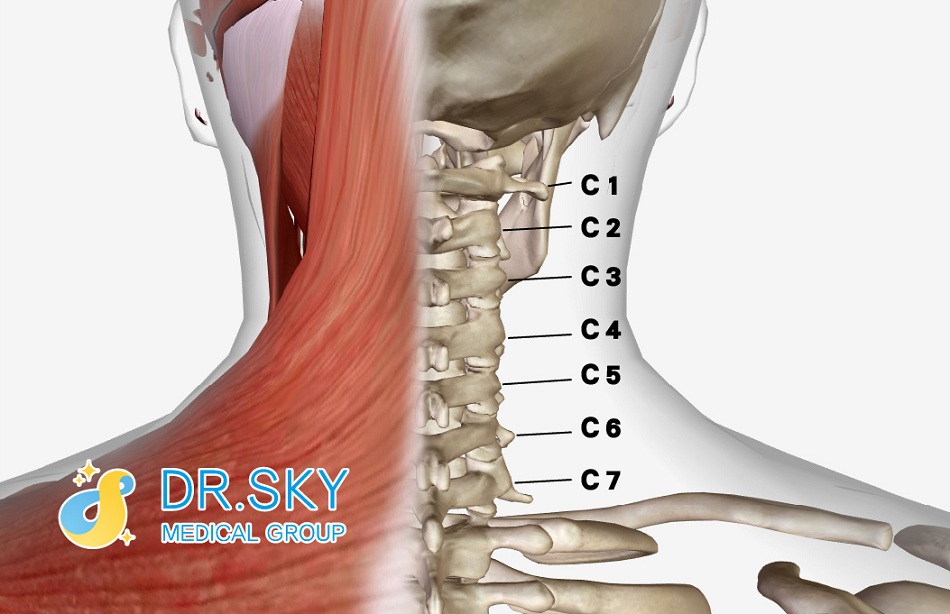

耳鳴成因相當複雜,每位病患的病情亦不相同,須仰賴醫師多年臨床治療經驗的判斷。一般除因自律神經失調引起內耳局部細胞發炎的耳鳴外,還有一個與耳鳴有關連的人體構造位置就是「頸椎」。首先,讓我們一起看看頸部的構造。

▲ 頸部肌肉及骨骼構造

頸部構造位於前方的是氣管、大動脈、大靜脈等結構,位於後方的主要是骨骼系統──脊椎,神經系統──脊髓,及活動伸展系統──肌肉及筋膜等軟組織構造。